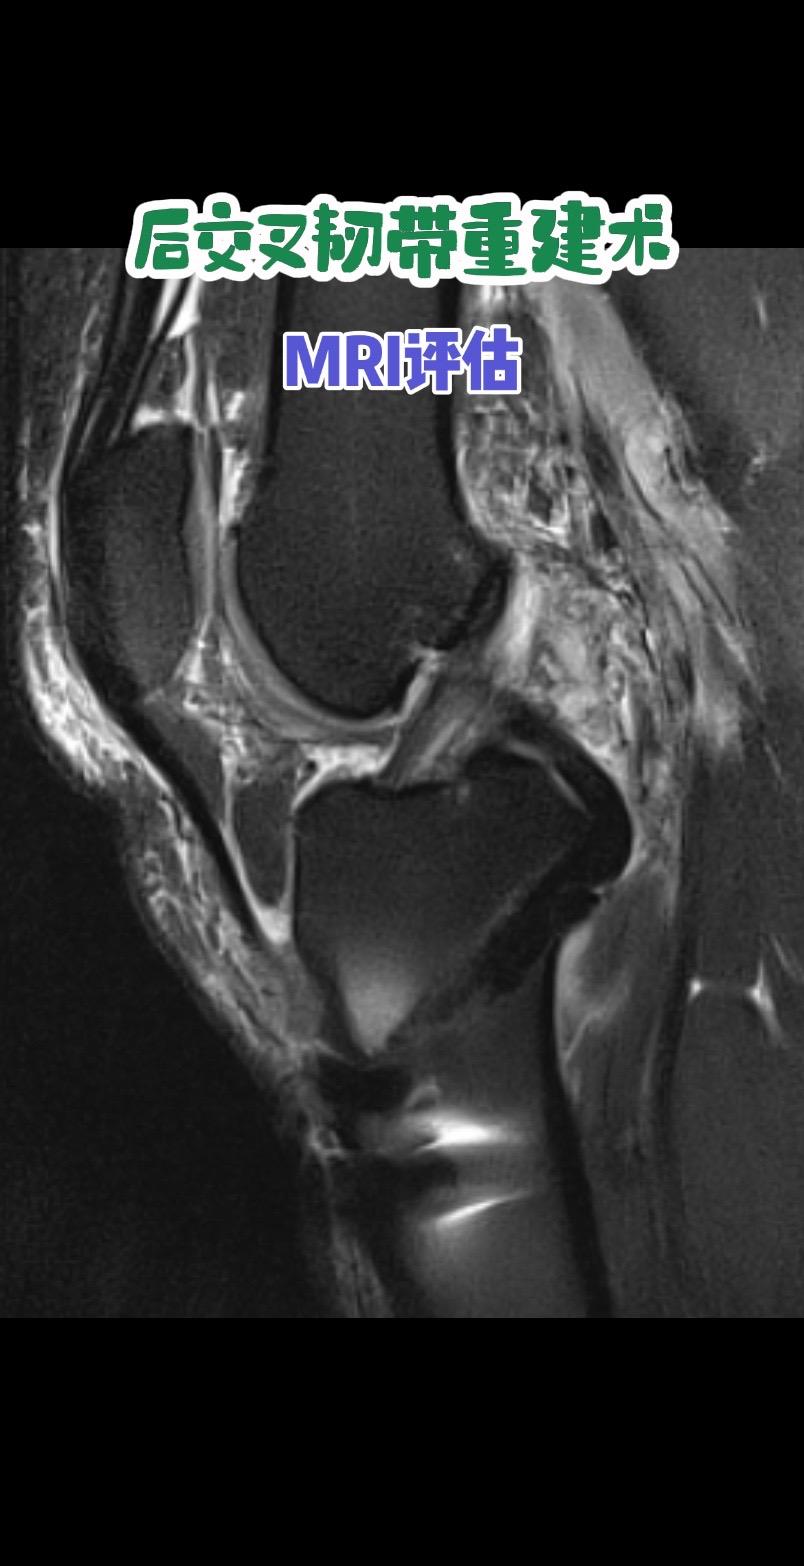

后交叉韧带重建术后影像评估。每一条韧带,都是膝盖的隐形安全带。而精准重建,就是给关节最可靠的浪漫守护。